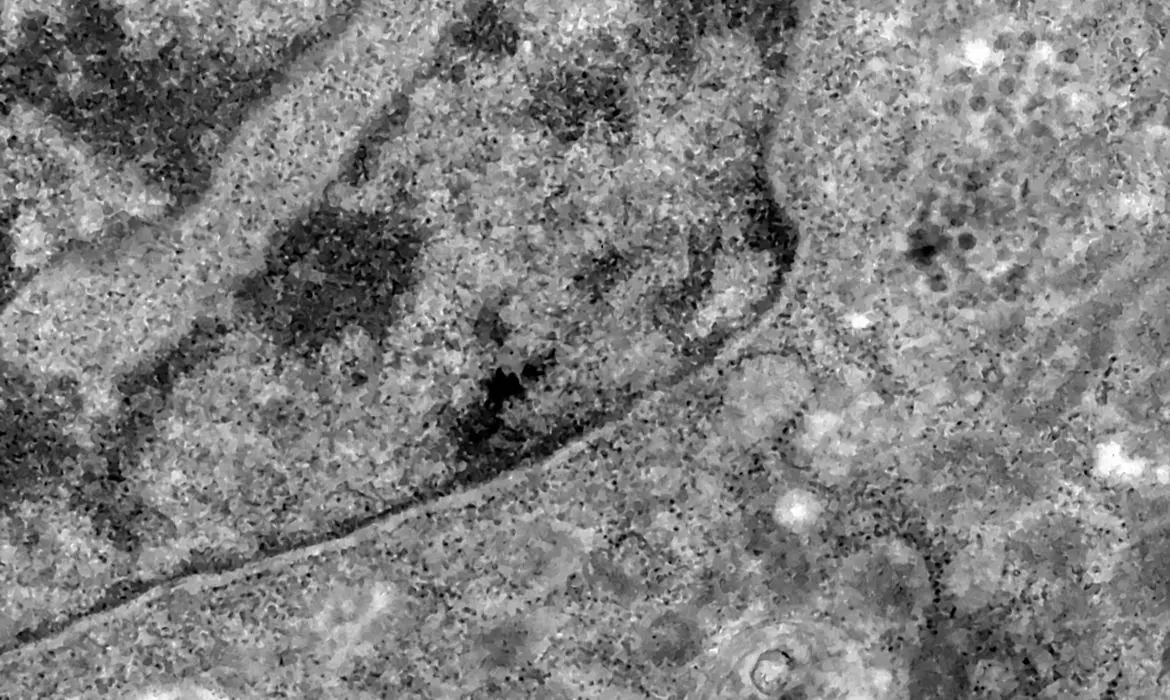

ômicron

Legenda: Variante do coronavírus foi descoberta na África do Sul

Foto: Débora Barreto/Fiocruz